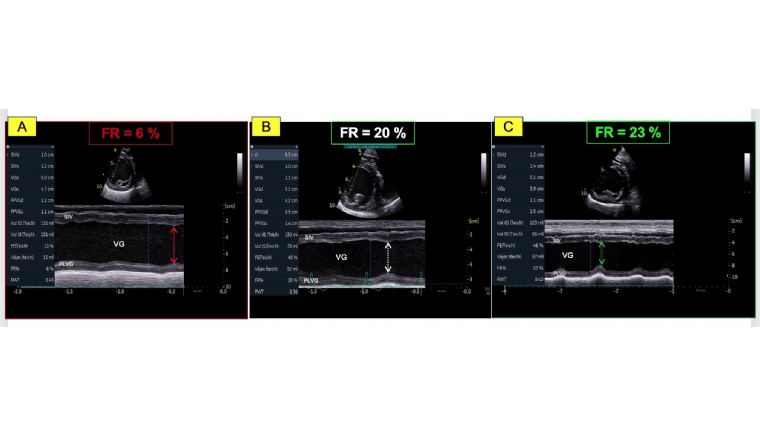

- La valeur très diminuée de la fraction de raccourcissement (FR) égale à 6 %; (valeurs usuelles (VU) 29%) (Figure 1A) ainsi que de la fraction d'éjection (FE) ventriculaire gauche égale à 16% ; (VU 42%) (Figures 2A et 2B) ;

- Une dysfonction systolique nettement améliorée avec une fraction d'éjection normalisée à J0 + 9 mois (Figures 2E et 2F, Tableau 2) malgré la persistance d'une hypokinésie radiale du septum interventriculaire qui contribue au maintien d'une fraction de raccourcissement diminuée mais de façon moindre (FR égale à 23 % à J0 +

9 mois versus 20% à J0+ 3 mois versus 6 % à J0 (Figures 1B, 1C et Tableau 2) ;

- Une diminution marquée en systole du volume et du diamètre ventriculaire gauche, lesquels restent néanmoins augmentés (Tableau 2 et Figures 1B et 1C versus 1A) ;